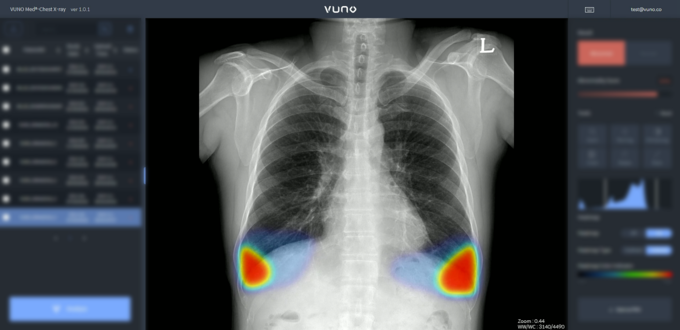

의료 인공지능(AI) 스타트업인 뷰노가 개발한 뷰노메드체스트엑스레이 활용 모습. 사진 = 뷰노 제공

의료 AI 솔루션 스타트업 뷰노는 높은 정확도로 패혈증 발생을 최대 12시간 전 예측하는 딥러닝 알고리즘을 선보였다. 지난달 28일 세계중환자의학회지(Critical Care Medicine)에 게재된 자체 개발 딥러닝 알고리즘 연구 논문은 데이터 예측에 다양한 변수 간 상관관계를 확인하는 기술을 적용해 패혈증 발생 예측 정확도를 높인 내용을 담고 있다.